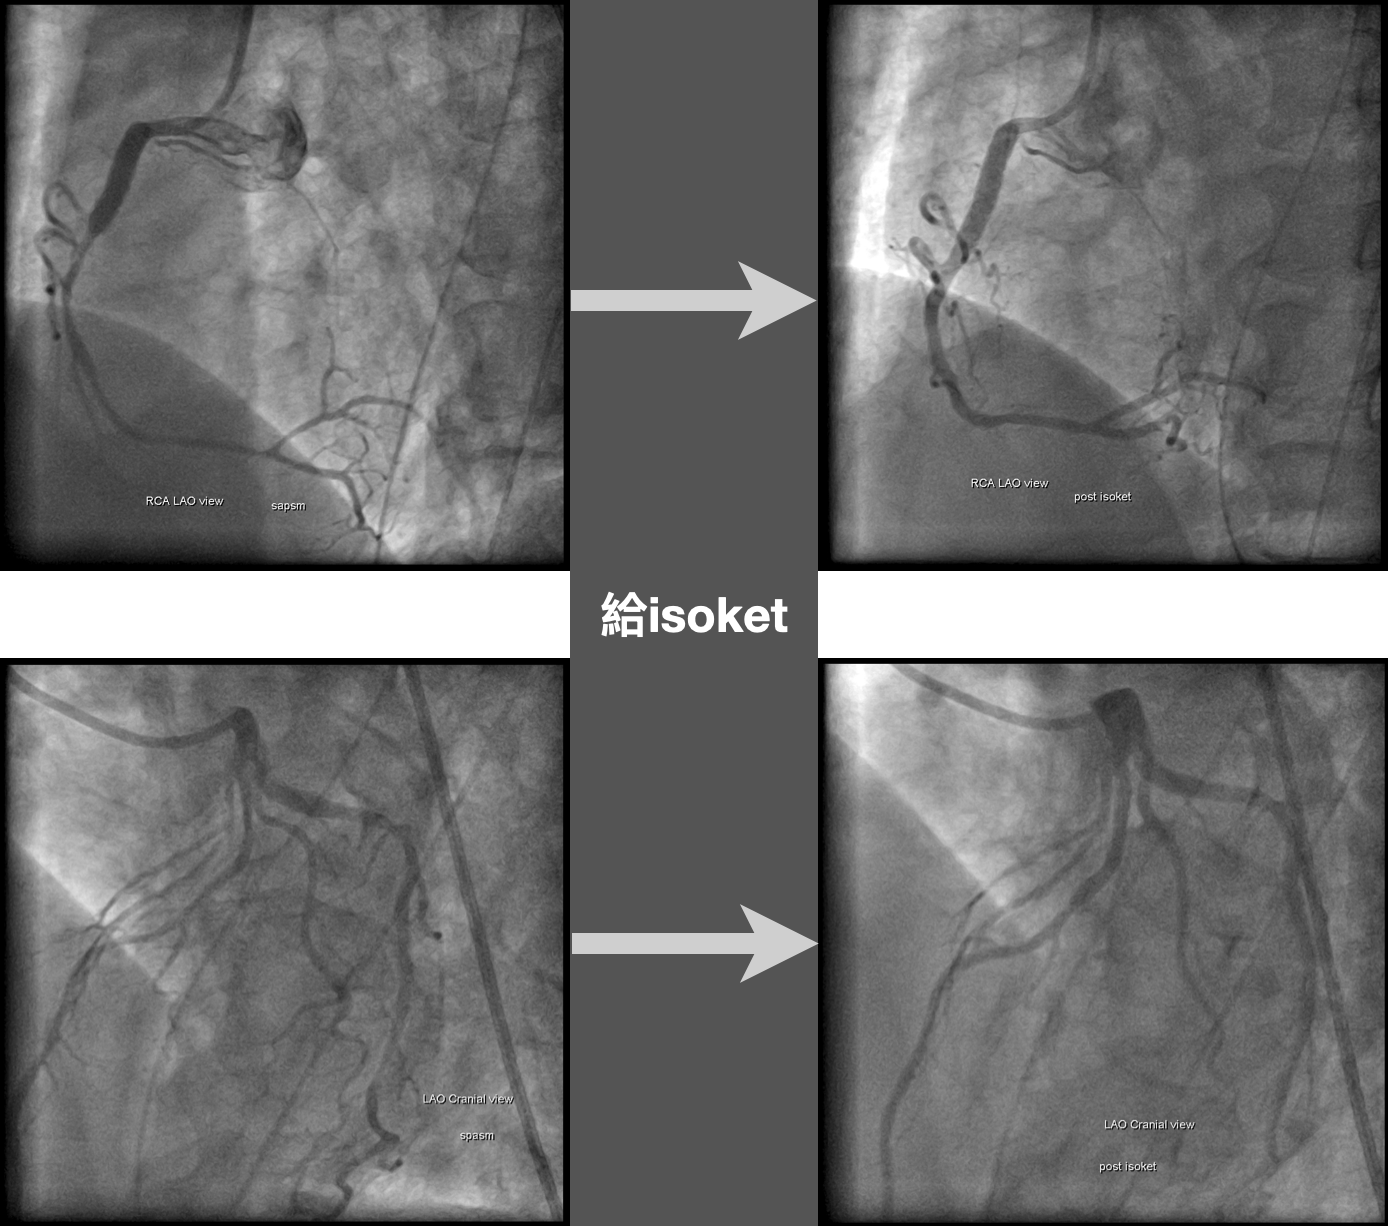

病患ROSC後,就被大批人馬從急診送到心導管室,進行進一步心導管檢查。

CAG檢查結果懷疑是coronary a. spasm引起。